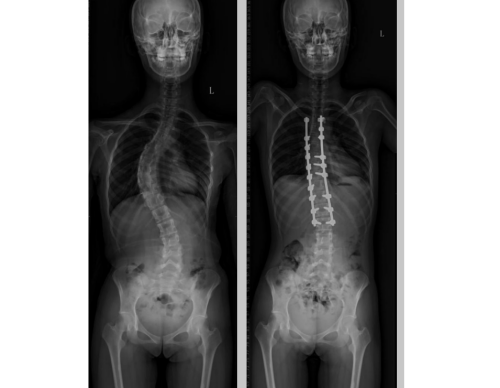

为了让孩子在寒假有充足的恢复时间,不耽误学业,许宇霞主任很快为小霞制定了详细的手术方案并进行了周全的术前准备,带领团队在春节前为小霞实施了矫正手术。术后,小霞的脊柱形态得到明显改善,在医护人员的精心照料下,逐渐恢复了健康,能够正常站立、行走,可以进行一些简单的运动。出院后,在医护人员的指导下,小霞恢复良好,将要挺直腰板迎来新学期。

术前 术后